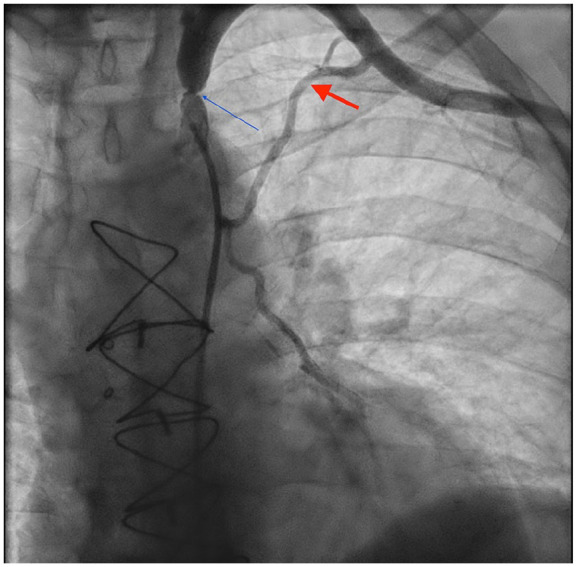

冠状动脉-锁骨下窃血综合征(CSSS)是冠状动脉旁路移植术(CABG)累及左乳内动脉(LIMA)后罕见但重要的并发症,通常是由于近端锁骨下动脉狭窄。我们报告一位54岁男性,既往有三支血管冠脉搭桥(LIMA至左前降),并发急性胸痛和肌钙蛋白水平升高。心电图示弥漫性st段改变。急诊血管造影显示移植物通畅,但左锁骨下动脉近LIMA起始处90%狭窄。病变通过经皮血管成形术和药物洗脱支架置入术成功治疗,症状得以缓解,心功能得以保留。CSSS虽然不常见,但在冠状动脉搭桥后复发性心绞痛或心肌损伤的患者中,尽管移植物未闭,仍应考虑CSSS。文献估计锁骨下狭窄高达5%的CABG候选者,但常规筛查仍然不一致。本病例强调了CSSS是一种可逆的缺血原因,并强调了在选定的患者中进行靶向血管成像的价值。

Coronary-subclavian steal syndrome (CSSS) is a rare but important complication following coronary artery bypass grafting (CABG) involving the left internal mammary artery (LIMA), typically due to proximal subclavian artery stenosis. We present a 54-year-old male with prior triple-vessel CABG (LIMA to left anterior descending) who developed acute chest pain and elevated troponin levels. Electrocardiogram showed diffuse ST-segment changes. Emergent angiography revealed patent grafts but critical 90% stenosis of the left subclavian artery proximal to the LIMA origin. The lesion was successfully treated with percutaneous angioplasty and drug-eluting stent placement, resulting in the resolution of symptoms and preserved cardiac function. CSSS, though uncommon, should be considered in post-CABG patients with recurrent angina or myocardial injury despite patent grafts. Literature estimates subclavian stenosis in up to 5% of CABG candidates, yet routine screening remains inconsistent. This case highlights CSSS as a reversible cause of ischemia and underscores the value of targeted vascular imaging in selected patients.